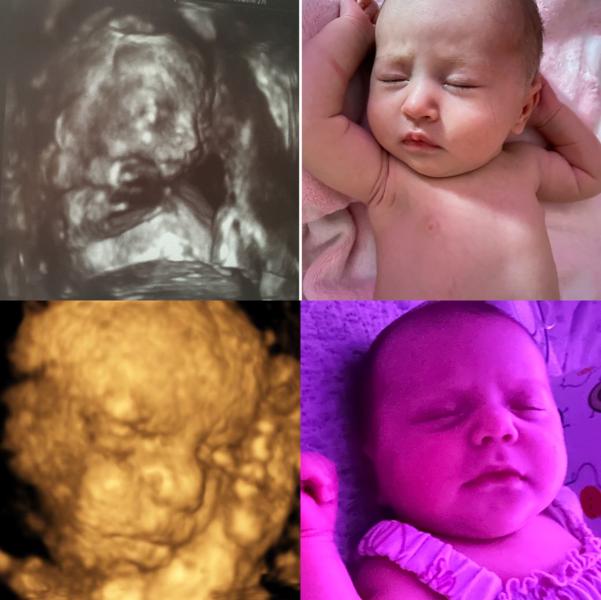

post image

👧🏻 Имя - Таисия / Алевтина

🚼 Пол - девочка/ девочка

⚖️ Вес - 2900/ 3085

📏 Рост 50 см/ 51

📊 Шкала апгар-9/10 / 9/10